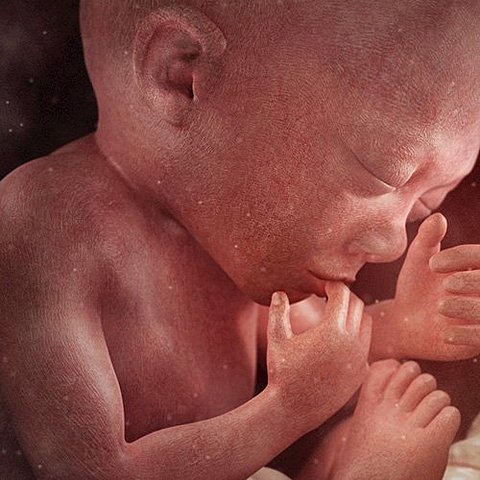

En la semana 25 de embarazo, el bebé ya tiene pestañas y abre por fin sus ojitos. Su lengua sale de la boca y se mueve hacia los lados. Su cabeza sigue siendo demasiado grande en comparación con el cuerpo.

Estamos en el septimo mes (semana 28). El sistema nervioso es capaz de controlar los movimientos respiratorios y la temperatura. Su estómago, intestinos y riñones funcionan perfectamente. Todos sus órganos sensoriales están despiertos. Los párpados y los ojos están completamente formados y comienzan a abrirse y cerrarse. Empieza a percibir los sonidos. Los ruidos intensos le aumentan la frecuencia cardíaca. En este mes comienza a presentar hipo.